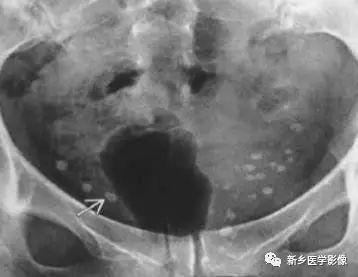

x线检查 多数正常,约1/4发现静脉石(图3),幼年开始患病者眶腔扩大及

静脉石11主要表现为点状的钙化,ct显示清晰,腹部平片